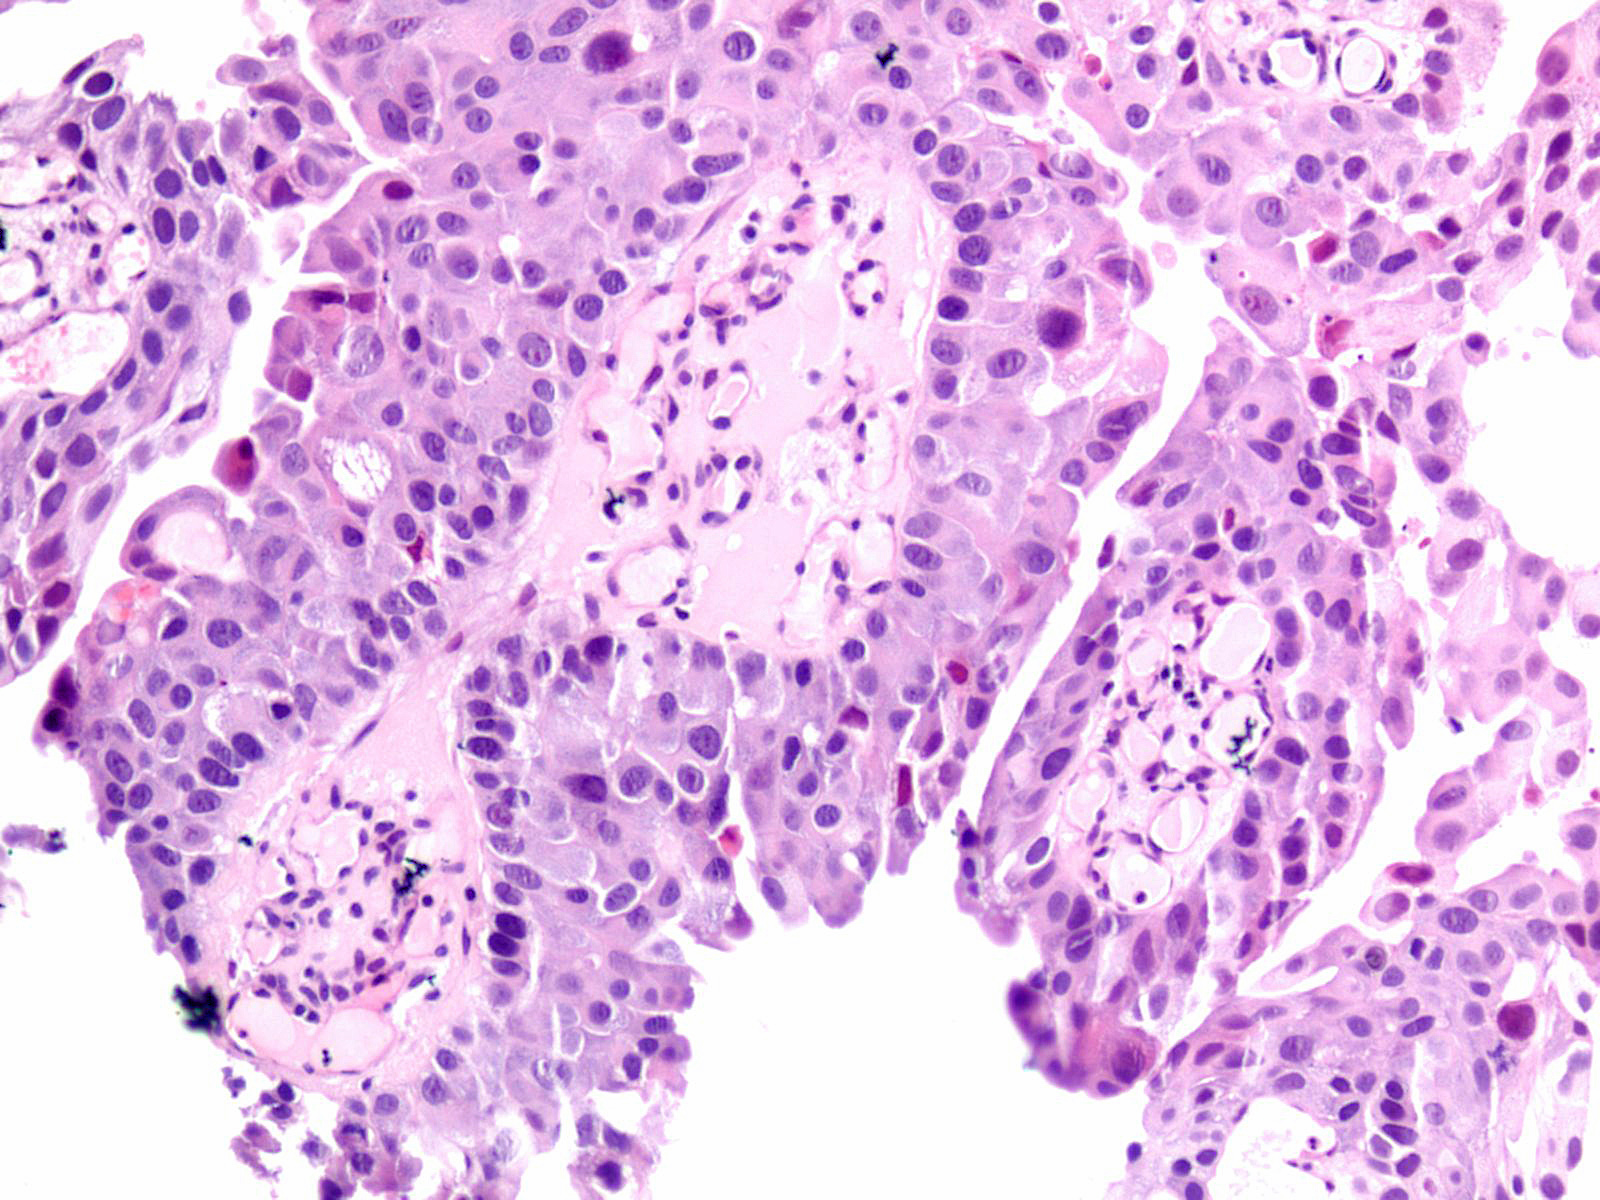

Consensus grade: High-grade papillary urothelial carcinoma (HG-PUC)

Lesion shows marked variation in nuclear size, shape and chromatin. Architecturally, cells appear loosely cohesive and the epithelium is disorganized. Mitotic figures are seen.